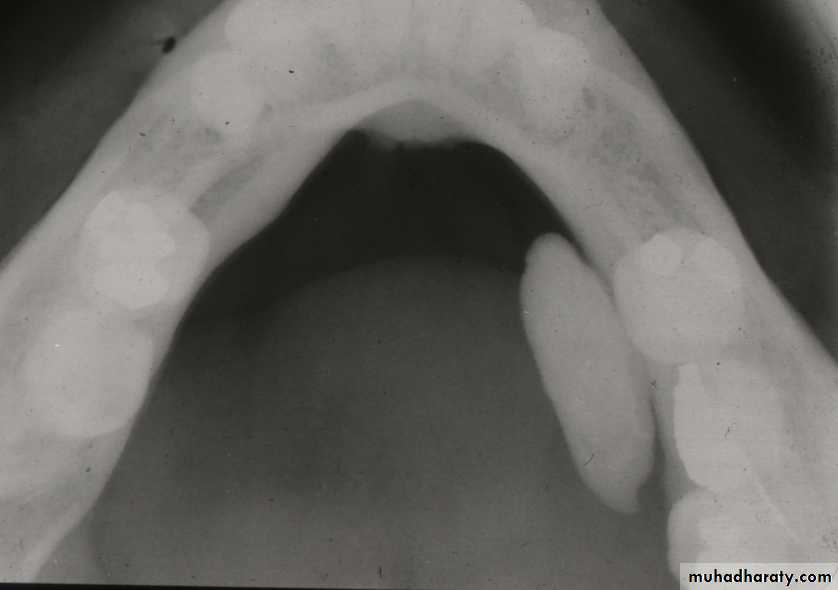

Parotid Gland - Sialolithiasis

DiagnosisBased on history

Swelling during meals

Bimanual palpation of painful gland

40% non-radiopaque

Most parotid stones are multiple

Sialogram